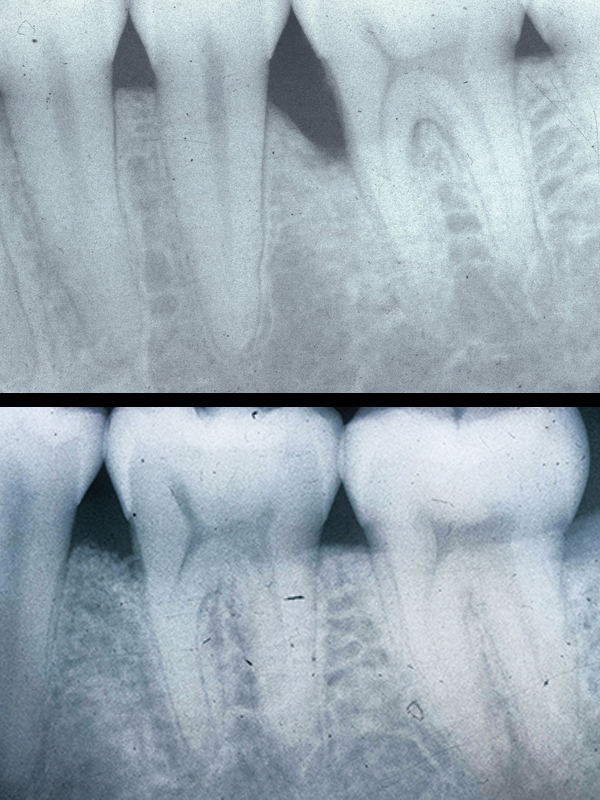

Periodontitis:

If gingivitis lingers, this infection drips down onto the bone holding in your teeth and begins to dissolve it away. This advanced disease is called “periodontitis”. As the bone disappears, a deeper crevice, known as a “pocket”, forms around the teeth. These deep pockets serve as “larger & larger nests” where more and more bugs grow, perpetuating more bone loss and eventually tooth loss.

One of the primary goals of periodontal treatment is to “reduce or eliminate the pocket”. In so doing, the patient is able to clean and thus prevent the return of the disease. There are 2 basic ways to achieve this. With mild forms of the disease, one may utilize non-surgical root planning. The more serious and advanced forms of disease require

surgical care.

Non-surgical Root Planing:

Mild forms of gum disease (gingivitis & early periodontitis) may be treatable by root planing. In root planing, the gums around the teeth are numbed and the infected root, under the gum line, is scaled & planed smooth, removing calculus, tartar, and plaque. In succeeding weeks, the tissues undergo a healing process and attach back to the tooth. In mild cases this process reduces the pocket depth to that of health, allowing the patient to effectively clean and maintain

their gums.